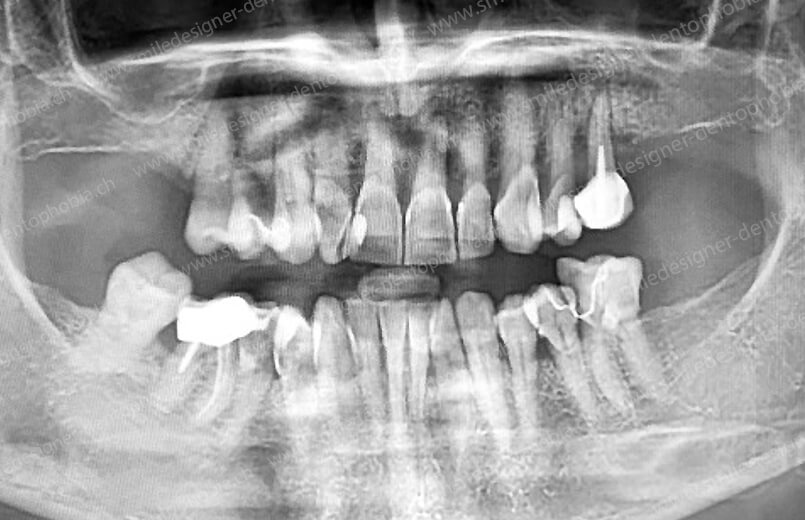

Cas clinique « GOLD STANDARD MCI » maxillaire : Bridge implanto-porté sans extension (ALL ON 8). Version définitive des bridges avec un cosmétique en céramique.